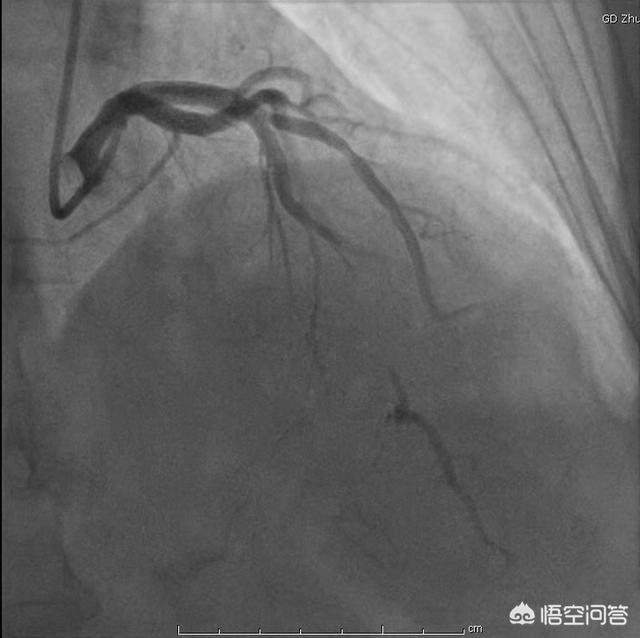

La maladie coronarienne est causée par l'ischémie, l'hypoxie et la nécrose du myocarde dues à la sténose ou à l'occlusion des artères coronaires pour diverses raisons. D'une manière générale, la maladie coronarienne peut être diagnostiquée lorsque le degré de sténose de l'artère coronaire est supérieur ou égal à 50 %. Le diagnostic des patients atteints de maladie coronarienne repose principalement sur des symptômes cliniques tels que l'oppression thoracique et la douleur thoracique, et est clarifié par des examens tels que l'angiographie coronarienne.

Tout d'abord, la maladie coronarienne désigne le déséquilibre entre l'apport sanguin des artères coronaires et la consommation d'oxygène du cœur, entraînant une ischémie et une hypoxie temporaires ou continues du myocarde et donc l'apparition d'angine de poitrine, d'infarctus, d'arythmie, d'insuffisance cardiaque, etc. en tant que manifestations cliniques de la maladie cardiaque. La base physiopathologique commune de la maladie coronarienne est l'athérosclérose des artères coronaires ; le diagnostic de la maladie coronarienne repose principalement sur les résultats de l'angiographie coronarienne ou de l'angiographie CTA ; si le degré d'athérosclérose coronarienne atteint le degré de rétrécissement luminal de plus de 50 %, on peut diagnostiquer une maladie coronarienne ; s'il y a athérosclérose des artères coronaires, mais que la sténose est inférieure à 50 %, on diagnostique une athérosclérose de l'artère coronaire.

La réalité clinique est que nous pouvons diagnostiquer une maladie coronarienne sur la base des symptômes du patient et des causes de la maladie coronarienne qu'il présente (par exemple, hypertension, diabète sucré, hyperlipidémie, etc.) Bien sûr, avec les résultats de la coronarographie ou de l'angiographie coronarienne par tomographie assistée par ordinateur, ce sera plus intuitif.

Le degré d'obstruction des vaisseaux coronaires est la donnée la plus intuitive pour les patients atteints de maladie coronarienne afin d'évaluer leur risque.Le critère actuel qui fait le plus autorité pour confirmer le diagnostic de maladie coronarienne est une sténose de 50 %.Mais les données doivent provenir de la coronarographie, et non du scanner coronaire, qui n'est pas particulièrement précis et présente une certaine marge d'erreur.

Comme il n'est pas possible de procéder directement à une coronarographie, nous devons procéder à une évaluation et à une analyse de la situation, ce qui nécessite des informations telles que l'âge du patient, ses antécédents médicaux, ses symptômes, ses signes et la durée de la crise, afin d'émettre un jugement préliminaire, puis effectuer des tests non invasifs, comme une électrocardiographie, une tomodensitométrie cardiaque ou autre, avant de décider si une angiographie est nécessaire pour confirmer le diagnostic.